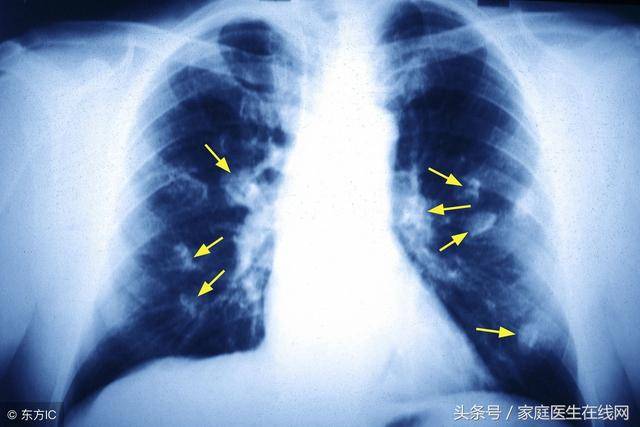

谈癌色变,大家都知道癌症是一种非常可怕的疾病,所以我们更在生活中尽可能地预防癌症的发生。今天我们来谈肺癌,到底患上肺癌的原因是什么?我们又要怎样去预防肺癌呢?跟着小编一起来看一看。

1、癌一个非常重要的原因就是遗传因素,如果有肺癌家族史,则肺癌的发病率较高。另外一个因素是吸烟,吸烟是目前与肺癌发病相关度最高的因素,吸烟人群中肺癌的发病率较之普通人群要高大概20倍,并且吸烟越多,发生肺癌的概率越大,包括二手烟、三手烟。长期吸烟导致支气管粘膜上皮细胞增生由此严重的影响到人体的肺部健康。

目前被认为是不吸烟人群中引发肺癌的首因。基础肺疾病,一些基础的肺疾病,主要是一些对正常肺组织产生刺激的非特异性炎症以及肺内瘢痕等,可促使癌变率增高:如尘肺、陈旧性肺结核等。